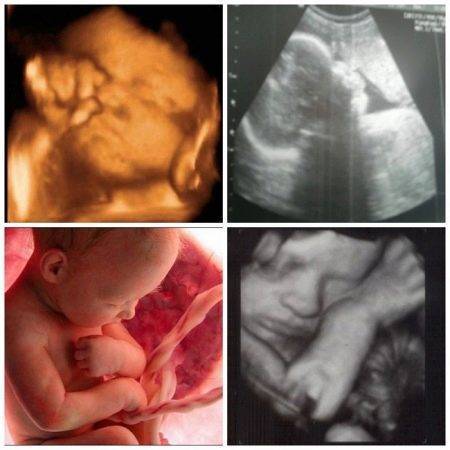

По согласованию с диагностом на второе УЗИ можно взять с собой и отца будущего ребенка. На мониторе сканера его ждет нечто довольно интересное, ведь теперь плод хорошо виден, можно полюбоваться его профилем, увидеть ручки и ножки, пальчики, нос, рот, глазницы, половые органы. Если УЗИ делается в 3D-формате, то будущие родители даже смогут увидеть, на кого больше похож карапуз.

Трехмерное и четырехмерное УЗИ делают дольше (40–60 мин). Зато будущая мама получает возможность посмотреть настоящий цветной фильм о своем малыше.

К восьмому месяцу беременности, когда плод сформировался, УЗИ показывает, что у него уже довольно хорошо развиты сердечно-сосудистая и центральная нервная системы, желудочно-кишечный тракт и мочевыделительная система, имеются все надлежащие признаки пола. Внешний облик малыша также претерпевает некоторые изменения – появляется волосяной пушок на голове, руки и ноги становятся более пухлыми, появляются выраженные щеки.